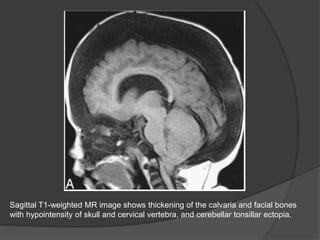

MRI

Sclerotic bone demonstrate low signal intensity on both T1- and T2-

weighted MR images;

Areas containing marrow have intermediate signal intensity.

Sagittal T1-weighted MR image shows thickening of the calvaria and facial bones

with hypointensity of skull and cervical vertebra, and cerebellar tonsillar ectopia.